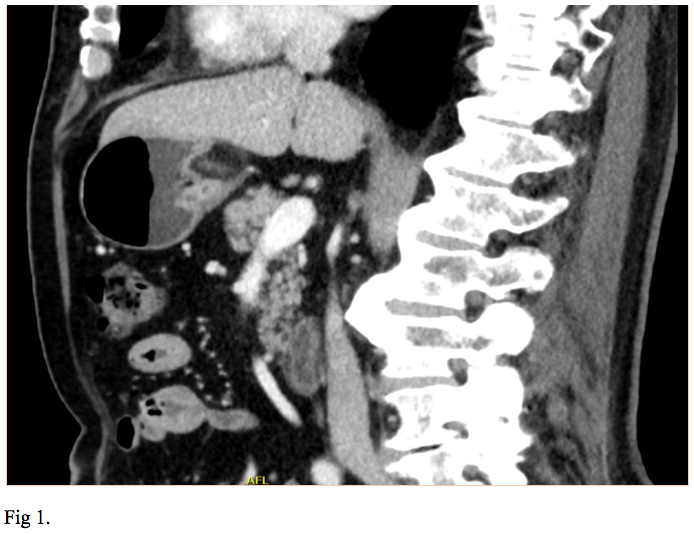

We report the case of a 66-year-old gentleman, known to suffer from high blood pressure, diabetes mellitus type 2, dyslipidemia, cervical and lumbar spondylosis, who presented to the emergency department with asthenia, pallor, melena. On physical examination, the patient was tachycardic with a heart rate of 120, and had a blood pressure of 100/60. He was pale but conscious and orientated. Cardiovascular and respiratory examinations were normal. His abdomen was soft, non-distended, bowel sounds were present and no palpable masses were felt. His laboratory investigations showed a mild normochromic, normocytic anaemia, low haematocrit, hyperglycemia, hypercholesterolemia. The patient was initially resuscitated and stabilized with intravenous fluids and proton pump inhibitors were initiated (iv 80 mg bolus and continuous infusion 8 mg/h). A naso-gastric tube was inserted which produced 300 ml of fresh blood. The patient underwent an urgent upper GI endoscopy which revealed an antral submucosal tumour with an ulcer over the mass. No active bleeding was seen during the procedure. A CT scan of the abdomen and pelvis highlighted a 30/20/18 mm oval shaped soft tissue lesion of fat density arising from the posterior wall of the stomach, with no associated lymphadenopathy. The liver, spleen, and pancreas all appeared normal (Fig 1,2). EUS has been performed and revealed a 30/18 mm intensely hyperechoic lesion continuous with the submucosal layer of the GI tract wall. The lesion was also soft on elastography, and as all the features were suggestive of a benign lesion, tissue sampling was not performed at that stage (Fig 3,4). The patient’s case was discussed at the Tumor Board meeting. The joint decision was to proceed with an exploratory laparoscopy and resect the benign mass. Histopathological examination confirmed the diagnosis of lipoma (Fig 5,6).

Regarding our case, based on the endoscopic appearance and location of the SELs, gastrointestinal stromal tumor (GIST), a neoplastic lesion with malignant potential was the most likely diagnosis. Differential diagnosis included surely benign lesions such as a lipoma, leiomyoma or schwannoma. The diagnosis of lipoma was suspected on abdominal CT scan and was confirmed by EUS. The joint decision to proceed with an exploratory laparoscopy and resect the benign mass was made based on the latest recommendation of the American Society for Gastrointestinal Endoscopy (ASGE). The suggestion of ASGE was that symptomatic GI lipoma should be resected or followed up.

Initial management of SELs centers on proper diagnosis and determination of any malignant potential of the lesion. EUS is the most accurate imaging test for evaluation of SELs of the GI tract. Lipoma is a well-defined hyperechoic lesion arising from the submucosal layer and does not require follow up or therapy unless is symptomatic.